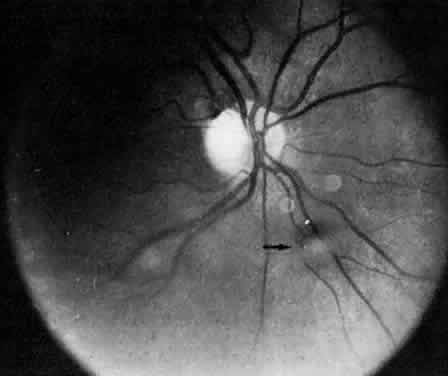

Retinal changes that can occur in pars planitis include perivascular sheathing of the retinal venules (periphlebitis), cystoid macular edema, and optic disc edema (Figs. 3 and 4). In cases of chronic cystoid macular edema, epiretinal membrane formation often occurs.4,13,27

Fig. 3. Pars planitis. Cystoid macular edema. Black arrows point to a halo of edema surrounding the macula. Open arrows point to cysts in the macula.